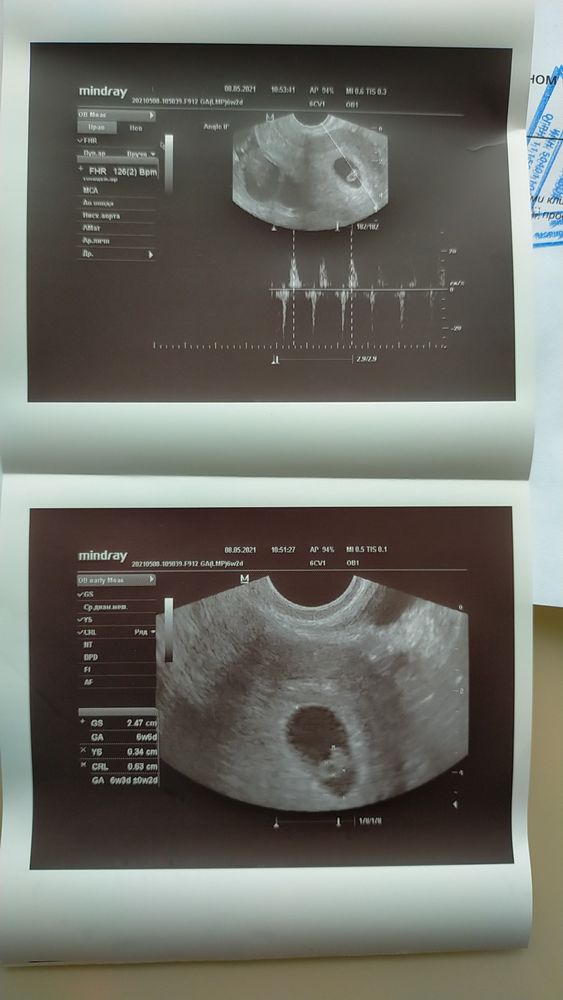

30 дпп УЗИ!

Я БЕРЕМЕННА !Всем привет. Ну вот и дождалась я наконец-то УЗИ , чтобы познакомиться с нашим малышочком🤗🤗🤗🥰

Поздравляю! :)) красивые фото малышочка тьфу-тьфу-тьфу :) растите здоровенькими! :)